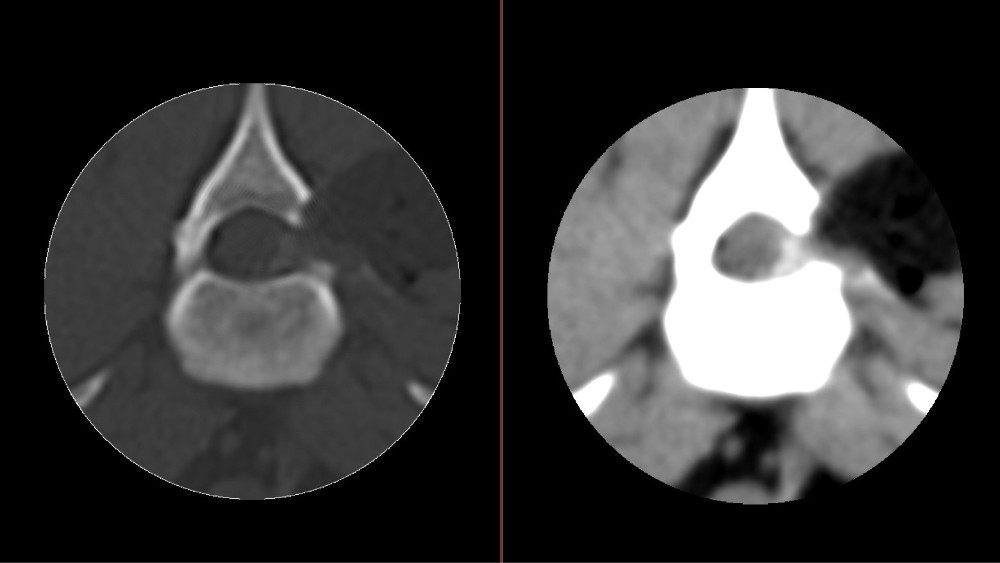

CT rechtsseitiger Bandscheibenvorfall Lendenwirbelsäule

CT rechtsseitiger Bandscheibenvorfall Lendenwirbelsäule: der verkalkte Bandscheibenvorfall nimmt auf der rechten Seite ca. 50% des Wirbelkanals ein und verdrängt so das Rückenmark stark.

CT Bandscheibenvorfall Lendenwirbelsäule postoperativ

CT Bandscheibenvorfall Lendenwirbelsäule postoperativ: nach der Entfernung des verkalkten Bandscheibenmaterials ist wieder genügend Platz für das Rückenmark im Wirbelkanal.